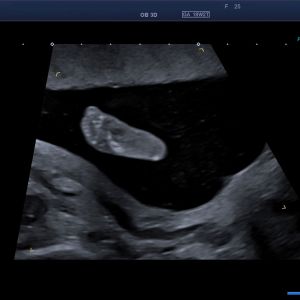

Schwerwiegende komplexe Herzfehler können schon im 1. Trimenon im Rahmen der frühen Fehlbildungsdiagnostik erfasst werden – optimaler Zeitpunkt zur Diagnostik von Herzfehlern ist die 20. - 22. SSW in Rahmen der Feindiagnostik (Organultraschall). Beurteilt werden die Lage des Herzens, die Herzkammern, die Herzklappen, die dem Herzen entspringenden Gefäße und der Herzrhythmus.